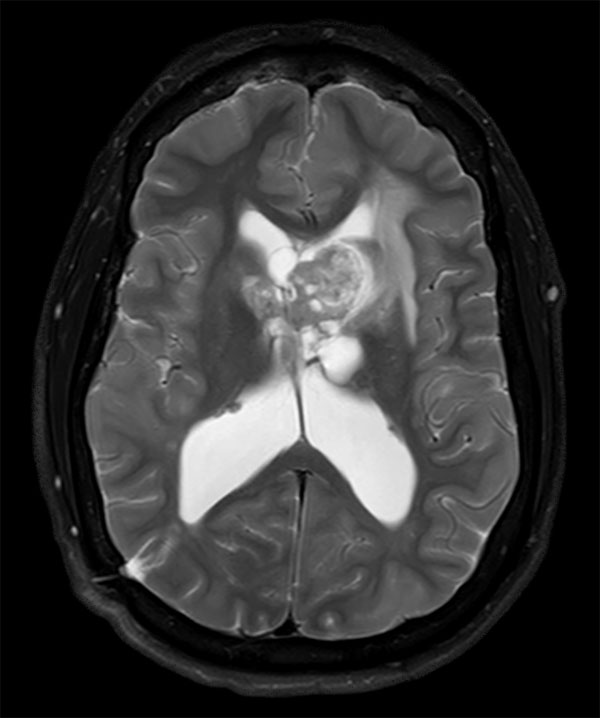

Axial T2w TSE